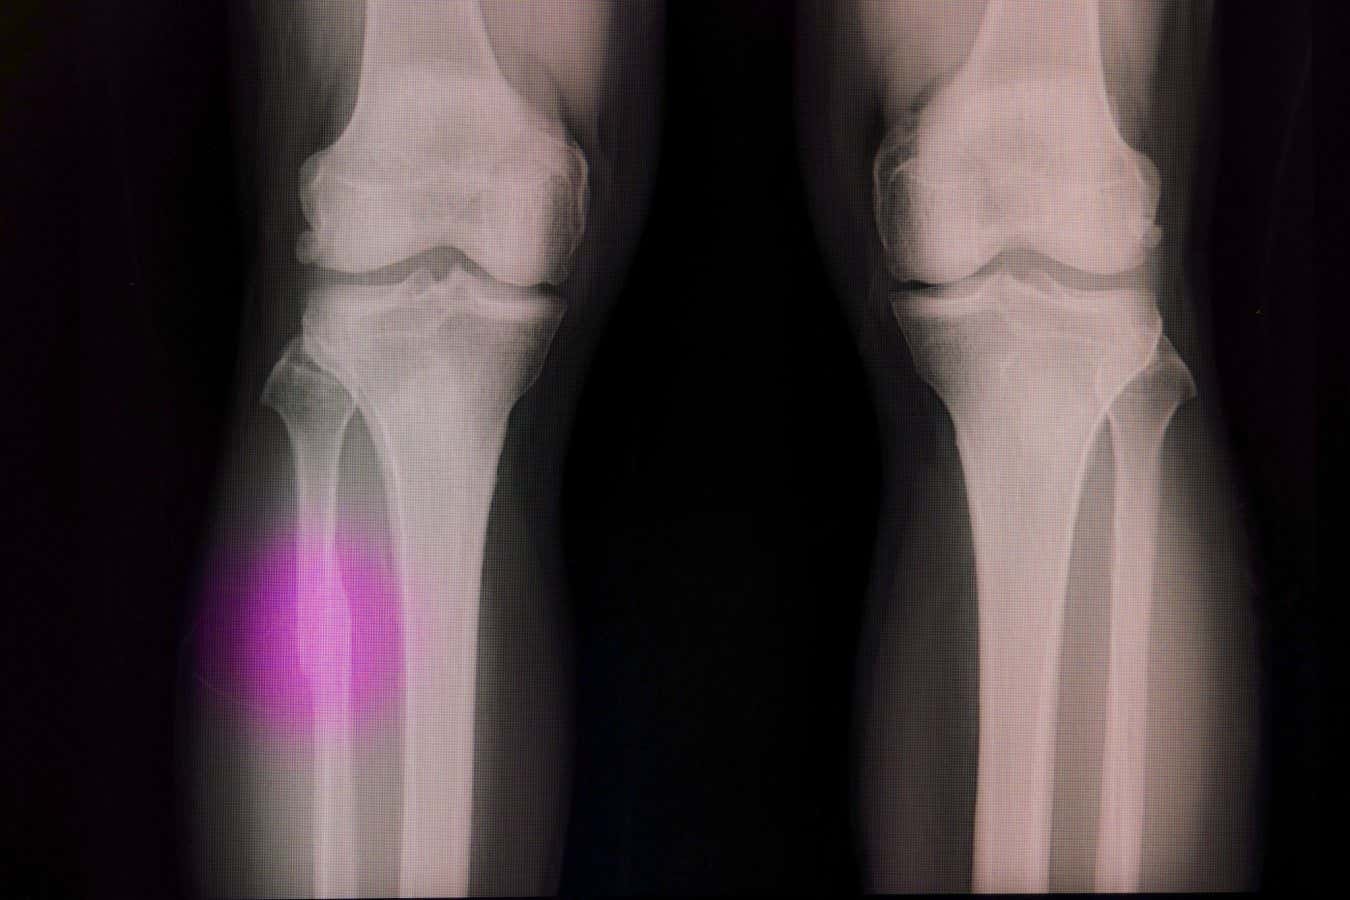

Broken bones often need a material to fill the void

Sopone Nawoot/Alamy

Bones can repair themselves after small injuries, but if there is a void – because of serious trauma or tumour removal, for example – then that space needs to be filled with either a graft or an artificial plug made of a material that encourages bone cells to spread.